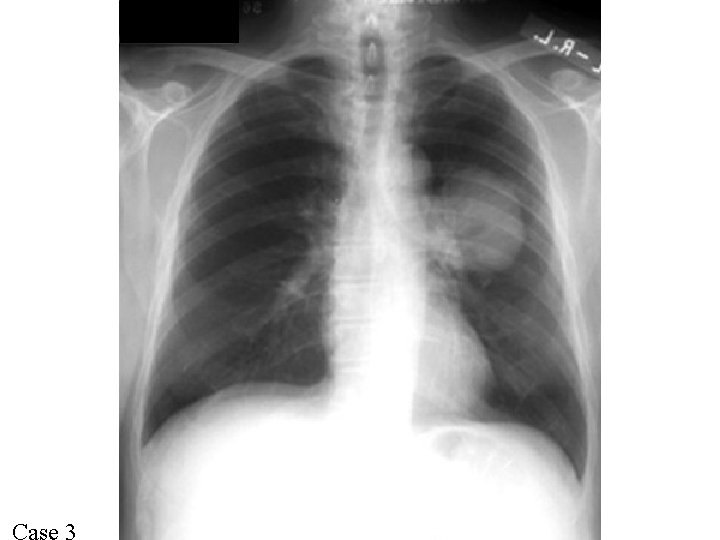

Case 7